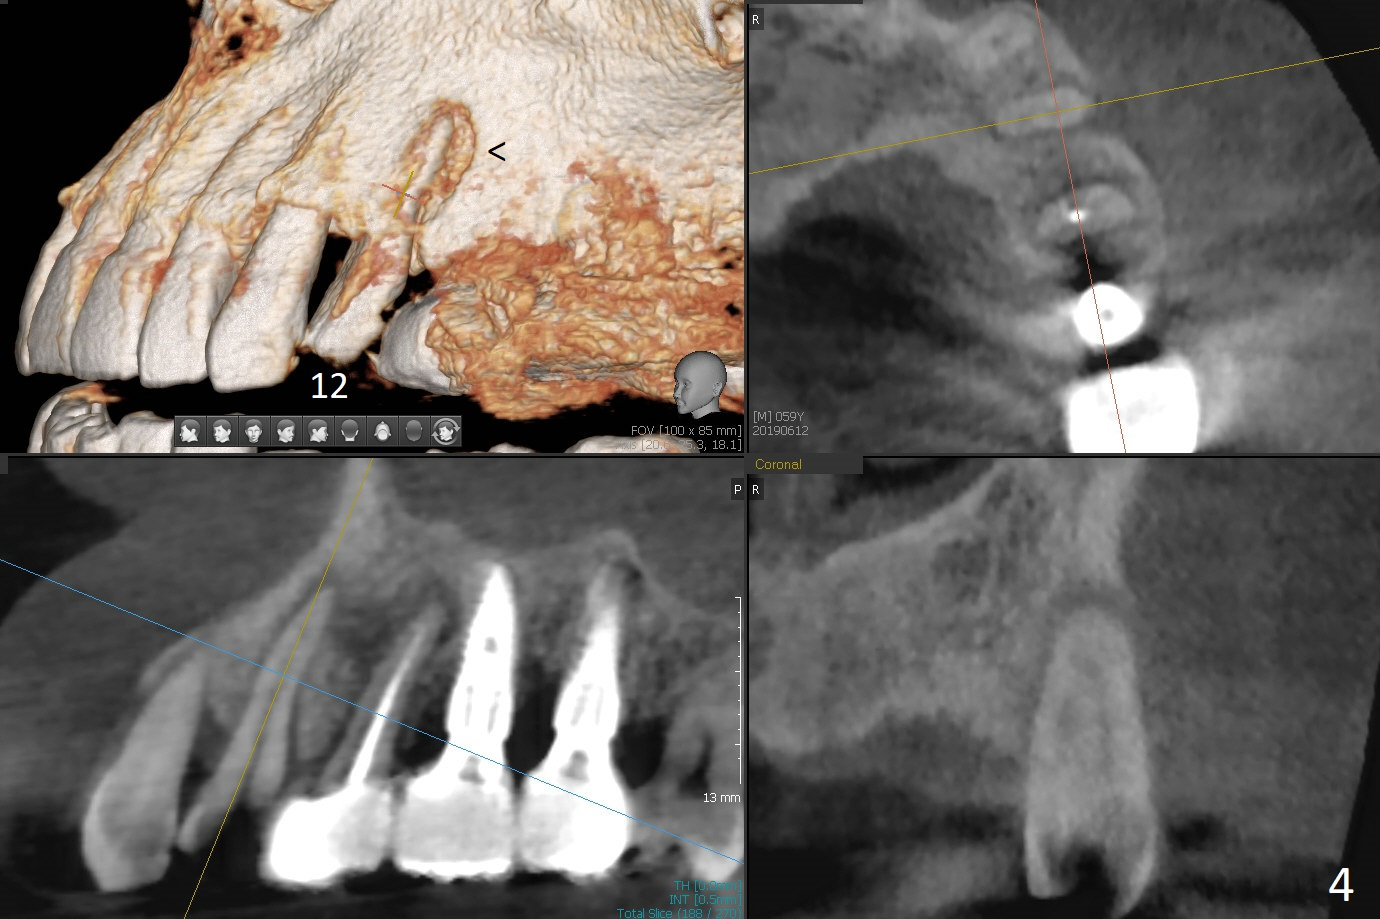

A 59-year-old man requests implant at #2 after those at #5, 14/15, and 29 (Fig.1). Sinus lift is required at #2 (Fig.2). Prepare PRF and SM implant (to be consistent with the previous ones without screw loosening). Although there is periapical radiolucency at #13 (Fig.3 >), there is another between #12 and 13 (Fig.3 *), which may be related to the apical infection at #12 (Fig.4 <).